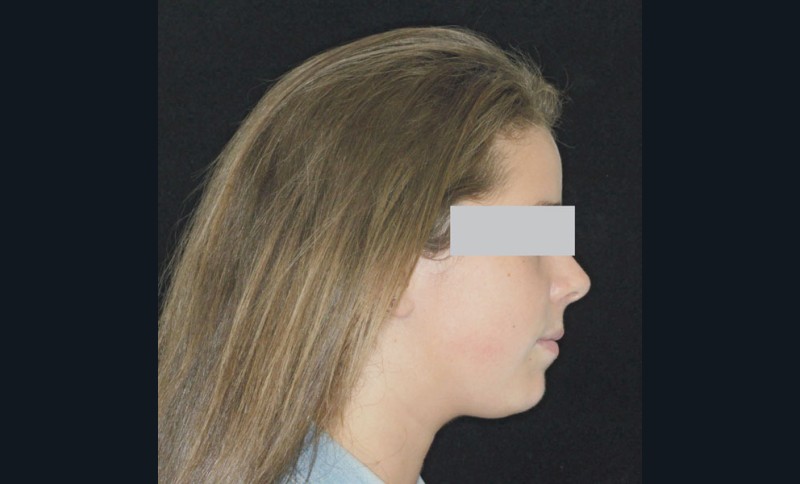

Son profil convexe s’inscrit dans un contexte de rétrognathie hyperdivergente associée à une proalvéolie et un encombrement maxillo-mandibulaire.